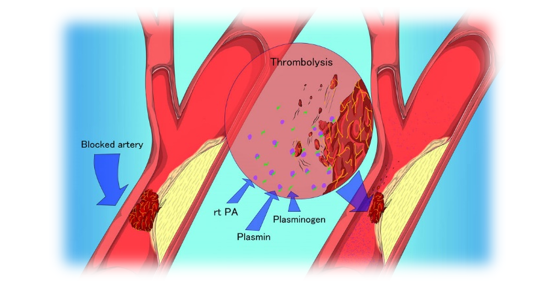

– Trombólise química no tratamento do AVC

FONTE: Interventional and Vascular Consultants.